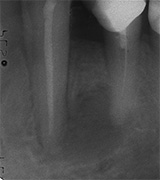

Der umfangreiche kariöse Defekt steuerte sehr bald hin auf die komplette Entfernung des Zahninnen­gewebes mit anschliessendem medikamentösen Wiederverschluss. Aufbissempfindlichkeit am Folgetermin ist immer Aufforderung zur erneuten Intensivsuche nach weiteren Kanälen, die hier einen 4. Ast zum Vorschein brachte. Nach 2 ausgelassenen Terminen

waren vorrangig Wiederherstellung von desinfizierender Einlage und provisorischer Füllung angezeigt. Eine weitere Woche später wurde in allen Kanälen das Medikament durch die endgültige Verschlussmasse ersetzt, worauf Zahn 36 mit 12-tägiger Verzögerung erneut zu rebellieren begann. Das hiess aus den hinteren Wurzeln Füllmaterial wieder raus und

Einlage erneut rein. Als es dann 4 Wochen später bei der hinteren Wur­zel aussen anzuschwellen begann und ein Medikamentenwechsel ohne Wir­kung blieb, wurden die hinteren Ka­näle abgefüllt und auch in gleicher Sitzung das überstopfte Material (Bild 1) mittels Resektion (Bild 2) von aussen entfernt.

Die ersten beiden Aufnahmen sind aus dem Jahr 1999, die 3. von 2006